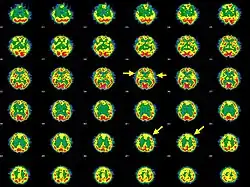

Среди симптомов энцефалопатии Хасимото — дезориентация, дрожь, нарушение памяти и концентрации внимания, миоклонические судороги, головные боли, частичный паралич половины тела, нарушение речи, генерализованные судороги,[8] психоз.[9][10] На ЭЭГ более чем в 90 % случаев отмечается перемежающаяся медленноволновая активность.[6][11] SPECT-сканирование мозга демонстрирует обратимую диффузную либо фокальную гипоперфузию,[12] хотя в одном случае, когда у пациента наблюдался эпилептический статус, была отмечена гиперперфузия правой париетальной области и височных долей.[13]

В одном обзоре пяти случаев авторы заявляют, что решающую роль в диагностике сыграло SPECT-сканирование, поскольку проявления синдрома были различны, а результаты морфологических тестов у пациентов не отличались от нормы; приводятся SPECT-изображения, иллюстрирующие возможности технологии.[16]